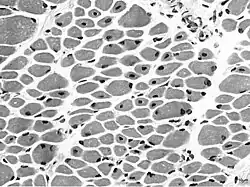

In der Muskelbiopsie sind bei allen Formen unreife Muskelfasern mit einer hohen Zahl zentraler Kerne auffällig, deren histologisches Bild an das fetale myotubuläre Entwicklungsstadium der Skelettmuskulatur erinnert. Es dominiert eine Typ-1-Muskelfaseratrophie.[5]